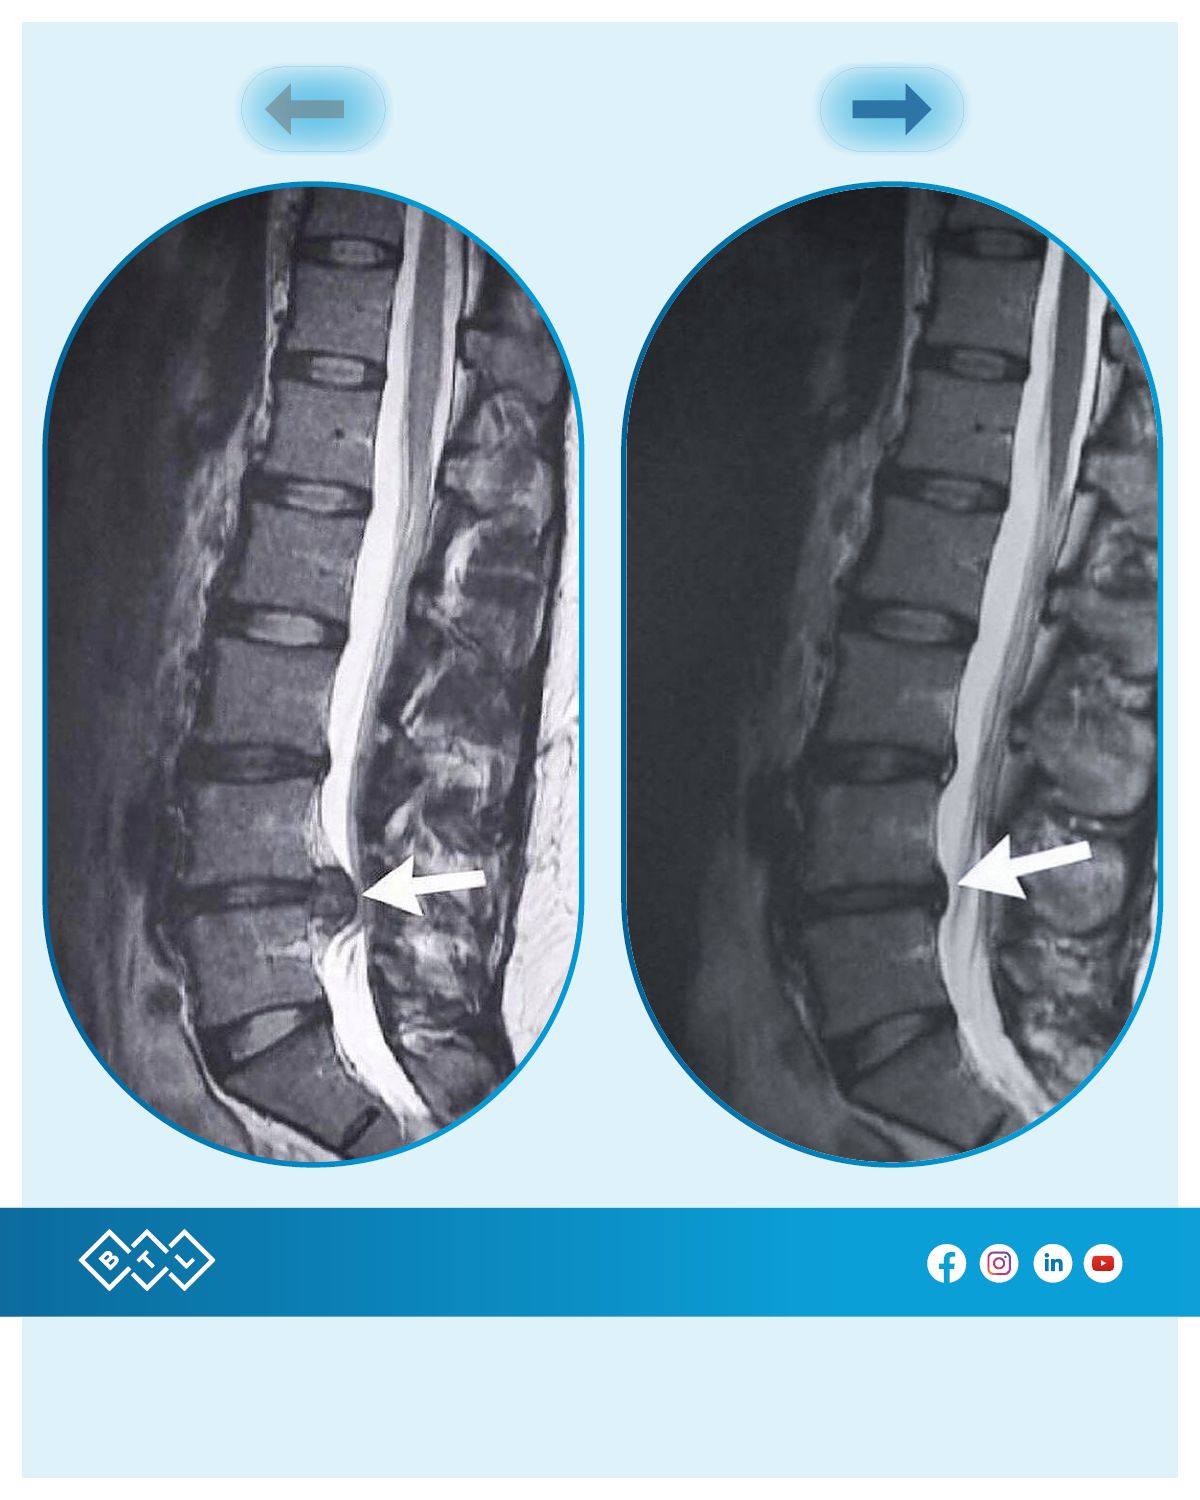

Presso il nostro studio è possibile effettuare l'innovativa terapia a DECOMPRESSIONE SPINALE NON-CHIRURGICA. Unica terapia nel suo genere presente sul territorio pontino.

La terapia è particolarmente indicata per il trattamento e la risoluzione di Ernie e Protrusioni sia Lombari che Cervicali, andando incontro molto spesso alla totale regressione dei sintomi nonché alla scomparsa dell'ernia o della protrusione. La terapia in molti può essere una soluzione alternativa NON INVASIVA all'intervento chirurgico. La vasta gamma delle applicazioni di tale terapia spaziano dalle discopatie all'artrosi, alle radicolopatie fino al classico mal di schiena o mal di collo.